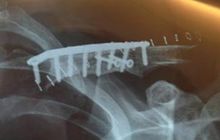

Musim terakhir Colin Edwards mengalami insiden cedera patah pada tulang selangka berturut-turut. Di MotoGP Catalunya tahun lalu, ia mengalami cedera tulang selangka sebelah kiri.